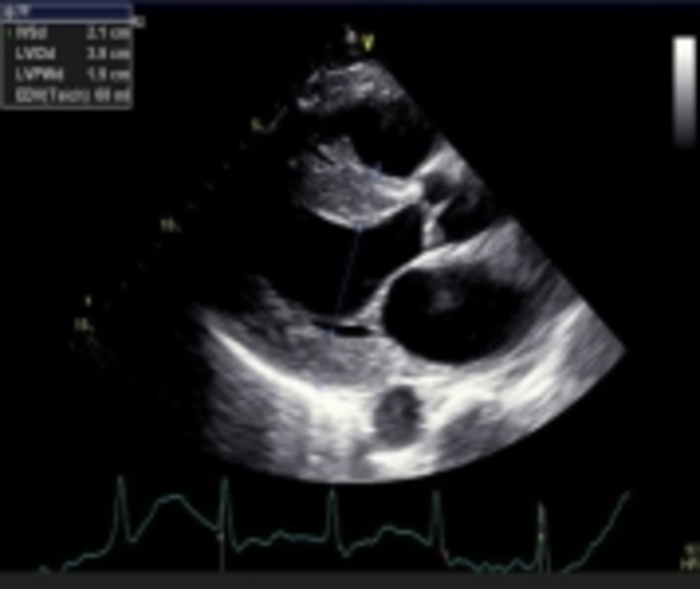

1. Echo imaging that reveals LV hypertrophy may be indicative of cardiac amyloidosis (CA)

2. GLS pattern of apical sparing is associated with CA